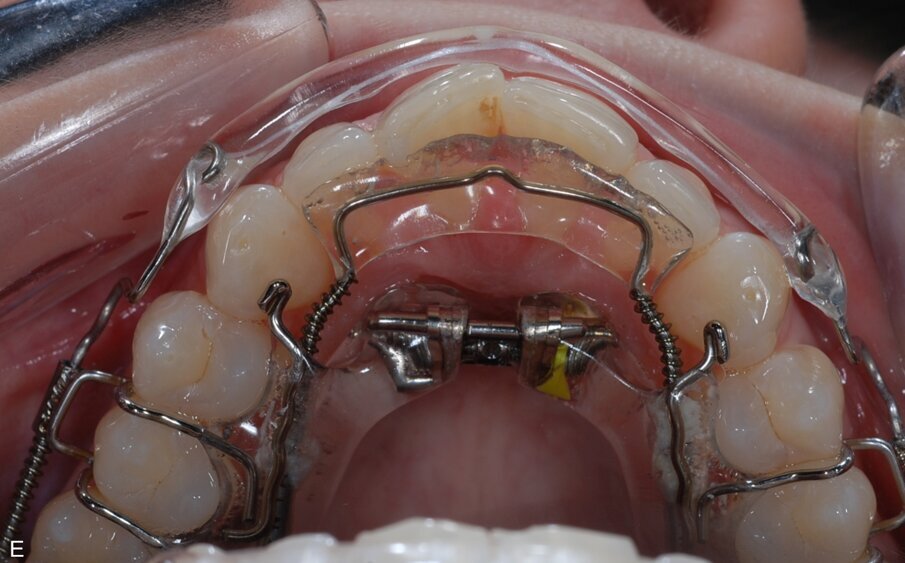

Fig. 9: ClearSmile Inman Aligner fitted

At the initial appointment, palatal anchors were placed, with interproximal reduction (IPR) and predictive proximal reduction (PPR) carried out using the guide issued from the laboratory. The patient was instructed on how to turn the expander. Aligner in situ. At the initial appointment, palatal anchors were placed, with interproximal reduction (IPR) and predictive proximal reduction (PPR) carried out using the guide issued from the laboratory. The patient was instructed on how to turn the expander. Aligner in situ. |